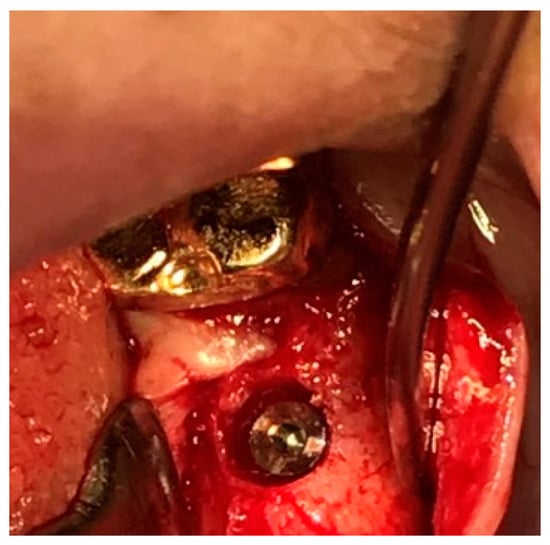

Figure 11 illustrates the step-by-step process of integrating pre-fabricated abutments with subcrestally placed healing abutments and the corresponding biological response of peri-implant soft tissue.

Figure 11.

Procedural steps for matching ready-made abutments with subcrestally placed healing abutments. The upper images include X-rays and clinical photographs, illustrating the process of matching ready-made abutments with subcrestally placed healing abutments. The lower images highlight the transitional zone (TZ) and subcrestal zone (SZ), showing their structural and functional differences. The TZ appears pink and elastic, while the SZ is paler and less elastic. Notably, the SZ forms after using a matching healing abutment due to its proximity to the adjacent subcrestal bone. Despite its thin structure, the SZ remains functional and stable, possibly due to its protected position beneath the TZ.

In the upper images, both X-ray and clinical photographs capture the procedural workflow involved in this process. These images demonstrate how ready-made abutments are carefully matched with subcrestally placed implants. The application of healing abutments plays a crucial role in shaping peri-implant soft tissue, ensuring a well-adapted emergence profile that facilitates long-term soft tissue stability.

The lower images provide a closer look at the peri-implant soft tissue structure following this process. Two distinct zones can be observed: the transitional zone (TZ) and the subcrestal zone (SZ). The TZ appears pink and elastic, indicating its dynamic adaptation to the implant’s emergence profile. In contrast, the SZ is paler and less elastic, positioned closer to the crestal bone, where it serves a more structural and stabilizing role. Unlike the TZ, the SZ is not naturally present, but is formed as a result of healing abutment placement, developing due to its proximity to adjacent subcrestal bone.

Despite its thinness, the SZ remains functionally stable, likely benefiting from its deep subcrestal location, where it is protected from excessive mechanical stress. The overlying TZ may further contribute to this protection, reinforcing the structural and biological stability of the peri-implant soft tissue.

This figure underscores the importance of healing abutments in peri-implant tissue adaptation, revealing how distinct soft tissue zones develop around implants and contribute to long-term stability and biological integration.